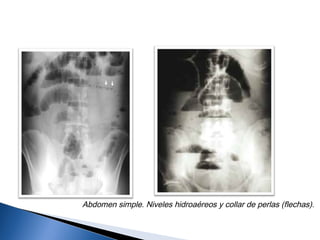

Abdomen simple. Niveles hidroaéreos y collar de perlas (flechas).